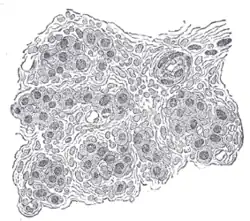

Corpuscule carotidien

Le corpuscule carotidien ou glomus carotidien[1],[2],[3] est un petit groupe de cellules chimioréceptrices et supportant les cellules sustentaculaires[4],[5].

Ce glomus est situé dans l'adventice en arrière de la carotide au niveau de sa bifurcation à la hauteur de la quatrième vertèbre cervicale.